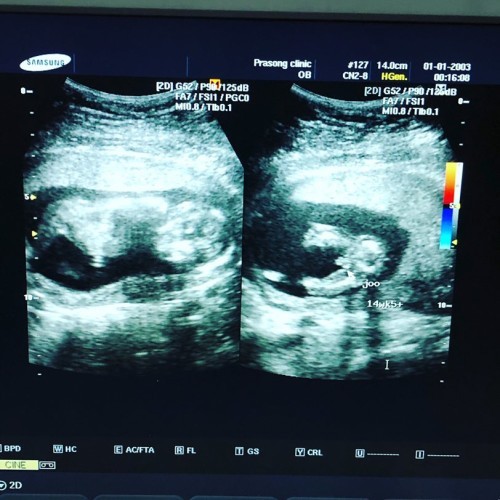

บ้านกำหนดคลอด30 มิถุนา. รู้เพศตอน14สัปดาห์ค่ะ เด็กผู้ชาย